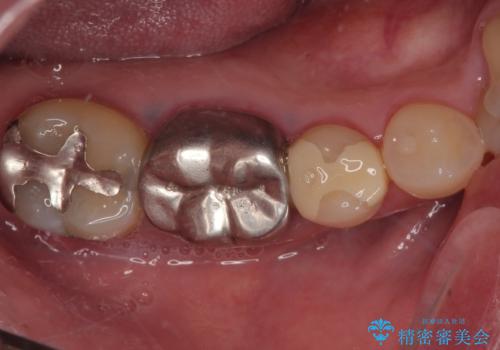

Dr. 中井遥香の症例写真

担当医 中井遥香<2026年2月2日更新>